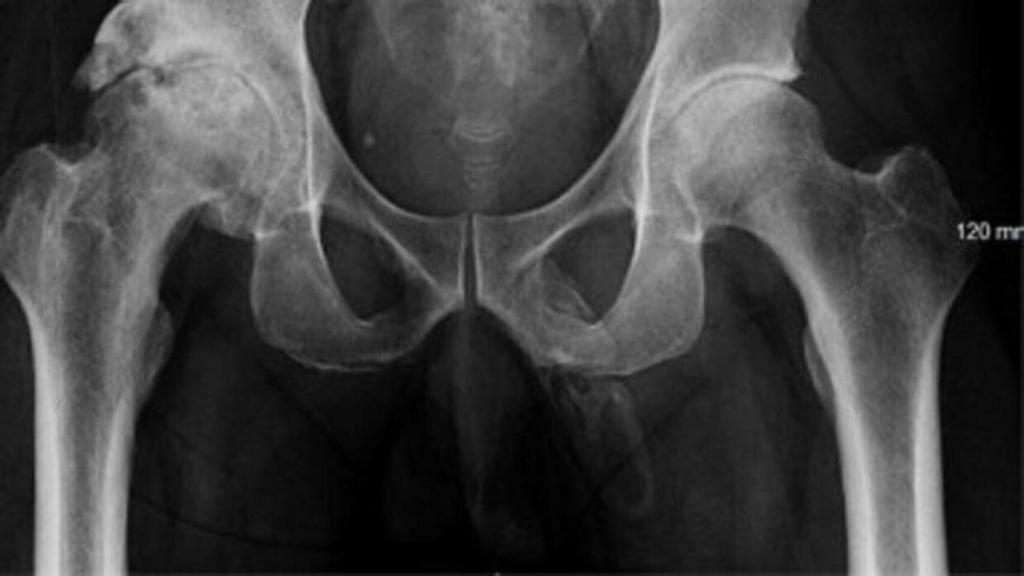

Radiografía de una cadera.

Los adultos mayores que viven en residencias suelen tener una ingesta baja de calcio y proteínas, lo que puede provocar la debilidad de los huesos y un aumento del riesgo de caídas y fracturas. Se calcula que los adultos mayores que viven en residencias son el origen de cerca del 30% de todas las fracturas de cadera.

Se analizaron los datos de 27 centros de intervención y 29 centros de control y se produjeron un total de 324 fracturas (135 de cadera), 4.302 caídas y 1.974 muertes durante el periodo de estudio.

La intervención se asoció a una reducción del riesgo del 33% para todas las fracturas (121 frente a 203), del 46% para las fracturas de cadera (42 frente a 93) y del 11% para las caídas (1.879 frente a 2.423). No hubo diferencias entre los grupos en cuanto a la mortalidad por todas las causas.